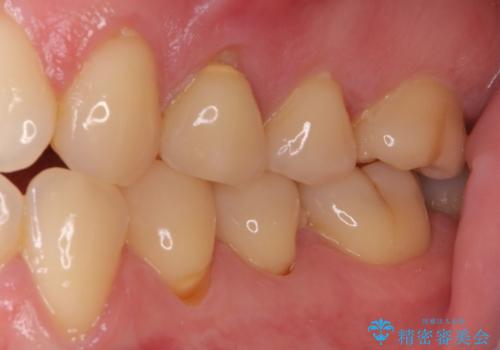

- 食事などで咬みこむと痛みを感じるとのことで来院された患者様です。

診査の結果、既に歯の神経は失活しており、レントゲンより根尖部に病変を認めました。

根管治療を行った後にオールセラミッククラウンにて補綴することとしました。